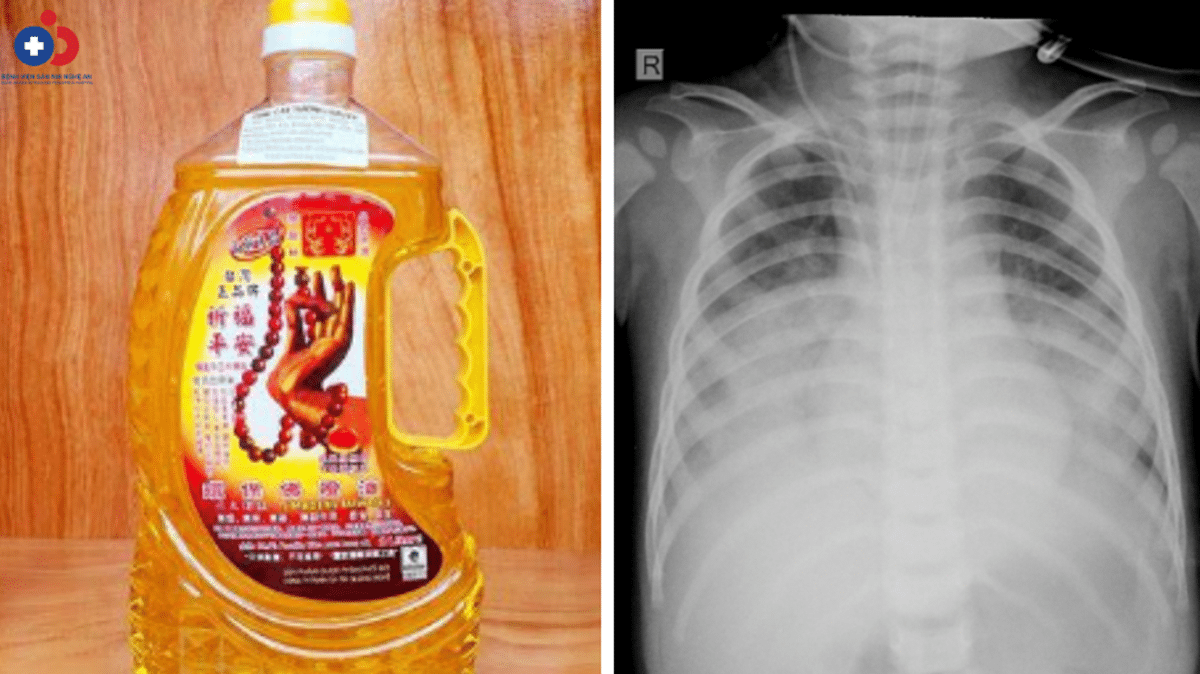

Sau khi uống phải dầu thắp đèn, bé 15 tháng tuổi tại Nghệ An tím tái, khó thở, rơi vào tình trạng nguy kịch dù nhanh chóng được đưa đi cấp cứu.

Theo người nhà bệnh nhi cho biết, trước khi vào viện 2h, bé T.N.H (15 tháng tuổi, Quỳnh Lưu) uống nhầm dầu thắp đèn trong khi chơi. Sau khi uống, bé bị sặc, ho, tím tái, khó thở. Người nhà lập tức đưa bé đến Bệnh viện trong thành phố Vinh cấp cứu. Tuy nhiên, tình trạng bệnh nặng, bệnh nhi tiếp tục được chuyển đến Bệnh viện Sản Nhi Nghệ An điều trị.

Khi được đưa vào Bệnh viện Sản Nhi Nghệ An, bệnh nhi trong tình trạng suy hô hấp, da tái, viêm phổi nặng… Các bác sĩ nhanh chóng hỗ trợ hô hấp bằng thở máy áp lực cao, dùng kháng sinh phổ rộng… Tuy nhiên, hiện bệnh nhi vẫn đang trong tình trạng nguy kịch, cần theo dõi.

Sau 3 ngày điều trị tại Bệnh viện tỉnh Bắc Giang, bệnh nhi được chuyển đến Bệnh viện Nhi Trung ương, nhập viện trong tình trạng tím tái, suy hô hấp, phải thở oxy. Sau khi thở oxy và dùng kháng sinh trong vòng 7 ngày, bệnh nhi tự thở lại bình thường nhưng ăn uống kém, tình trạng phổi còn tổn thương…